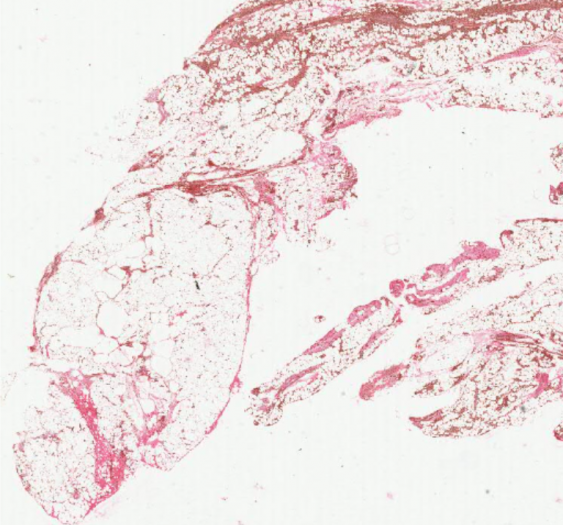

细胞和组织的适应与损伤

破裂的硅酮假体